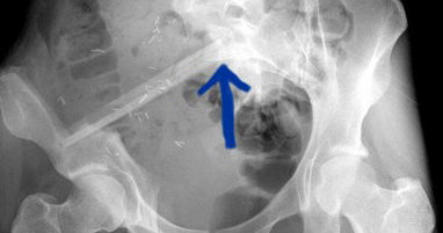

vermelden. Ich erinnert euch alle an die Bilder, die wir euch nach der Operation gezeigt haben. Hier ist es auf dem Foto noch einmal zu

sehen. Es ist ihr operativ das rechte Wadenbein aus dem Bein entfernt und als Stütze in das Becken eingesetzt worden, dort, wo vorher

die Beckenschaufel war. Das ist schon ein Meisterwerk ärztlicher Kunst gewesen. Und Gott hat Gelingen und Segen dazu gegeben. Die

Schmerzen, die Puschel in den letzten Tagen mehr hatte als sonst, rühren jetzt daher, dass der Knochen etwa an der Stelle, auf die der

Pfeil zeigt, richtiggehend durchgebrochen ist. Die Ärzte sprechen von einem Ermüdungsbruch. Der Knochen ist in der Substanz während

der Zeit der Chemo und der dadurch beabsichtigten Verhinderung der Neubildung von Zellen (Zielpunkt waren natürlich die

Krebszellen) zurückgegangen und ermüdet. Das große Problem ist, dass nun noch weniger Stabilität da ist und der Knochen erst wieder